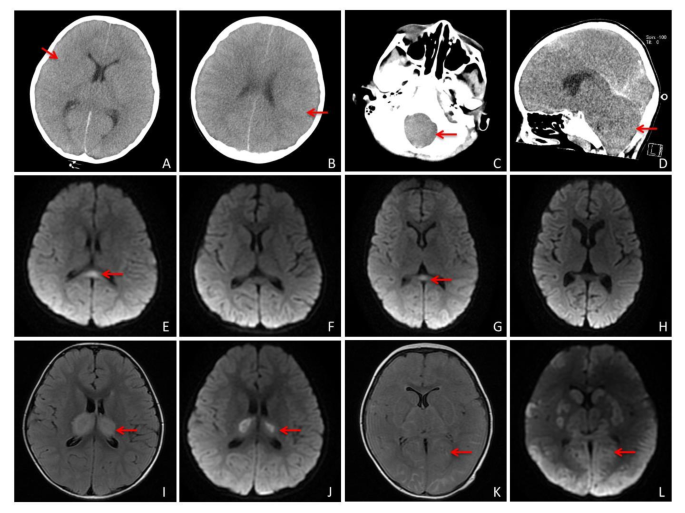

We included some of the respiratory symptoms and neurologic manifestations to assist in the evaluation of these children with IAE, with no statistically significant difference between the poor prognosis group and the clinically cured group in terms of cough and stuffy/runny nose. Almost all children had fever (96%), but there was no statistical difference between the two groups in terms of whether or not they had fever (P > 0.05). We included Glasgow coma scale, cranial imaging, and electroencephalography (EEG) to assist in assessing the neurologic performance of children with IAE. Among them, the Glasgow coma scale was significantly lower in the poor prognosis group than in the clinically cured group (7 vs. 12, P < 0.001), suggesting that the deeper the coma, the worse the prognosis may be. All patients underwent magnetic resonance or computed tomography during hospitalization, in which most of the children showed acute brain swelling (46%), followed by acute necrotizing encephalopathy and mild encephalitis/encephalopathy with a reversible splenial lesion, and one of them developed brain herniation. However, there was no statistically significant difference in imaging between the two groups. EEG was performed during the hospitalization of all patients, in which the EEG was predominantly slow wave (62%), 90% of the clinically cured group was predominantly slow wave, whereas the EEG of the group with poor prognosis mostly showed electrostatic resting and slow wave, which suggests that this part of the children had already entered into deep coma and the combination of severe brain injury, and even brain death may eventually occur (Table 3; Fig. 2).

Analysis of common cranial images of influenza-associated encephalopathy. Panels (A) and (B) Computed tomography of the brain showing diffuse brain swelling with poorly demarcated gray-white matter suggestive of acute cerebral swelling. Panels (C) and (D) Showing brain swelling with foramen magnum occipitalis hernia. Panels (E) through (H) Showing DWI sequences of magnetic resonance images (MRI) of mild encephalitis/encephalopathy with a reversible splenial lesion, where (E) and (G) are the initial images, and (F) and (H) are the follow-up images with lesion disappearance after 1 week. Panels (I) through (K) MRI showing acute necrotizing encephalopathy, with T2 Flair sequences in Figures (I) and (K), and DWI sequences in Figures (J) and (L), showing that the main lesion is located in the thalamic region.